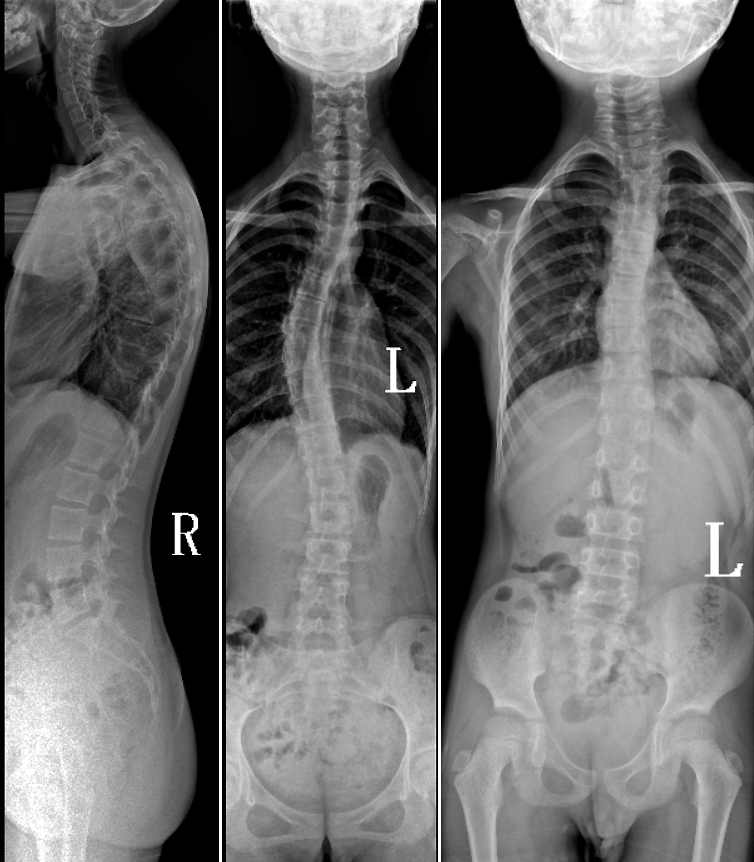

DR是臨床骨科的重要檢查手段之一。在骨科檢查中,脊柱矯形、長骨骨折、腰椎退行性病變等,需要采集脊柱、下肢全景圖像,輔助醫(yī)生臨床診斷,從而制定科學的治療方案,普愛醫(yī)療的大視野平板動態(tài)DR就像是一座橋梁,連接起現(xiàn)代醫(yī)療技術與當?shù)厝嗣竦尼t(yī)療需求。

普愛醫(yī)療自主研發(fā)的大視野平板動態(tài),采用17"*34"的有效視野,一次曝光即可得到全脊柱或全下肢影像。相較于多張攝影再軟件拼接的DR設備,PLX8600解決了拼接圖像存在密度不均勻,拼接處圖像配準和放大效應等問題,給臨床帶來了真正的大視野影像解決方案。

除了常規(guī)靜態(tài)攝影外,PLX8600的大平板具備動態(tài)透視和點片功能,能夠很好地觀察復雜部位病灶,有效地抓取關鍵幀,降低患者多次攝片的概率。如:全脊柱狀態(tài)評估、長骨關節(jié)活動度、下肢靜脈造影瓣膜功能評估、消化道功能評估、脊髓造影等更多大視野臨床應用,“多面手”都能輕松應對。